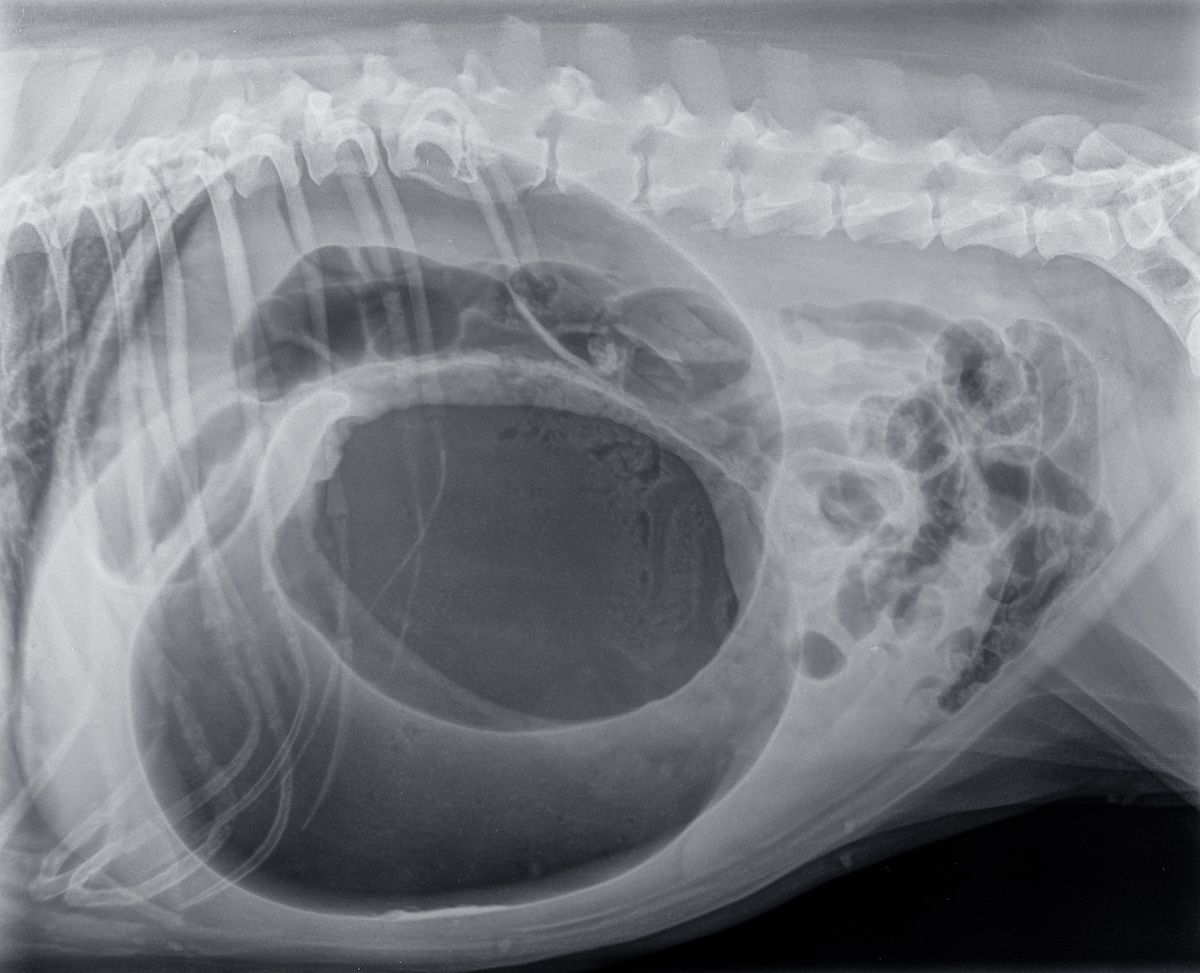

She encouraged both pet owners and practitioners to be proactive, explaining that it’s better to assume it’s GDV, assess it, and rule it out, rather than assume the gagging is simply a sign of nausea. An x-ray of a dog’s right lateral abdomen can confirm a GDV diagnosis, with Pace explaining that it will be immediately obvious when it’s GDV, as there will be a large pocket of air in the abdomen.

“We usually warn people that if they have any of these signs in a dog, [they should] just bring it in,” Pace said. “Worst case scenario, we can do an x-ray, and 1 x-ray can be a quick diagnostic that will tell us [whether] this is a problem, or if it’s something else that’s bothering them, and maybe it’s not a surgical emergency.”